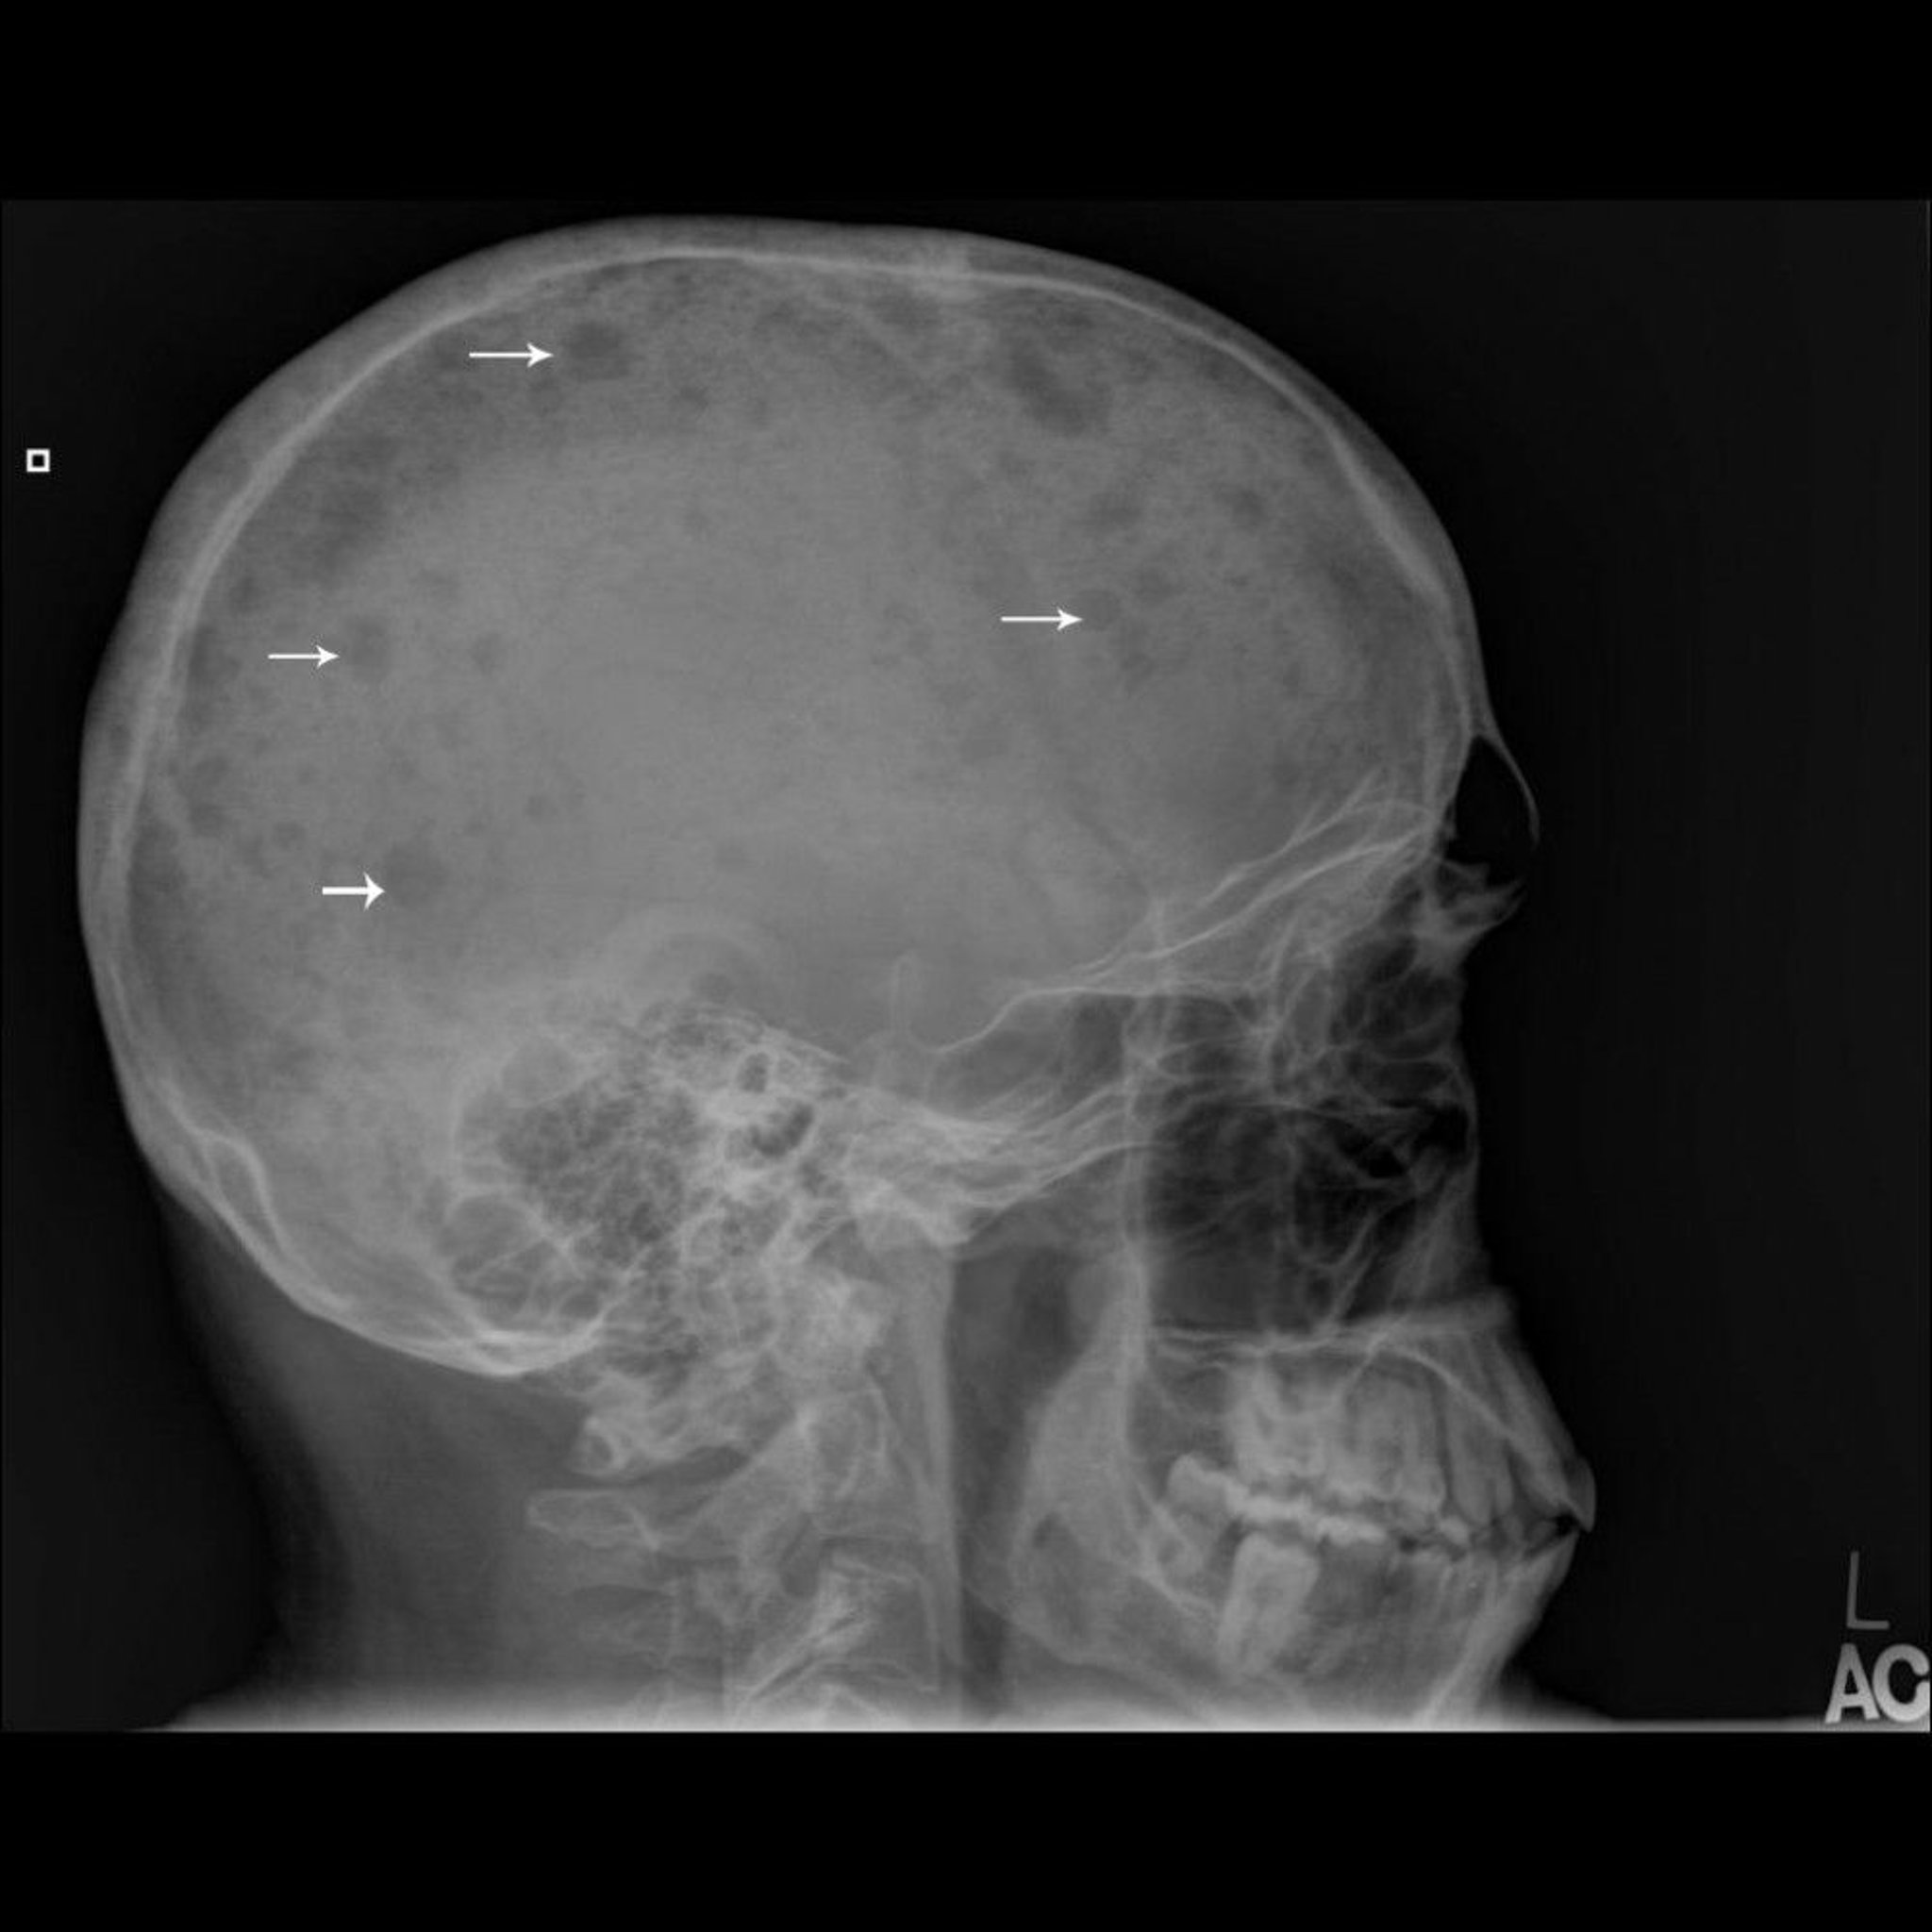

Essa radiografia do crânio mostra múltiplas lesões perfuradas no osso (setas), típicas do mieloma múltiplo.

Imagem cedida por cortesia de Michael J. Joyce, MD, and Hakan Ilaslan, MD.